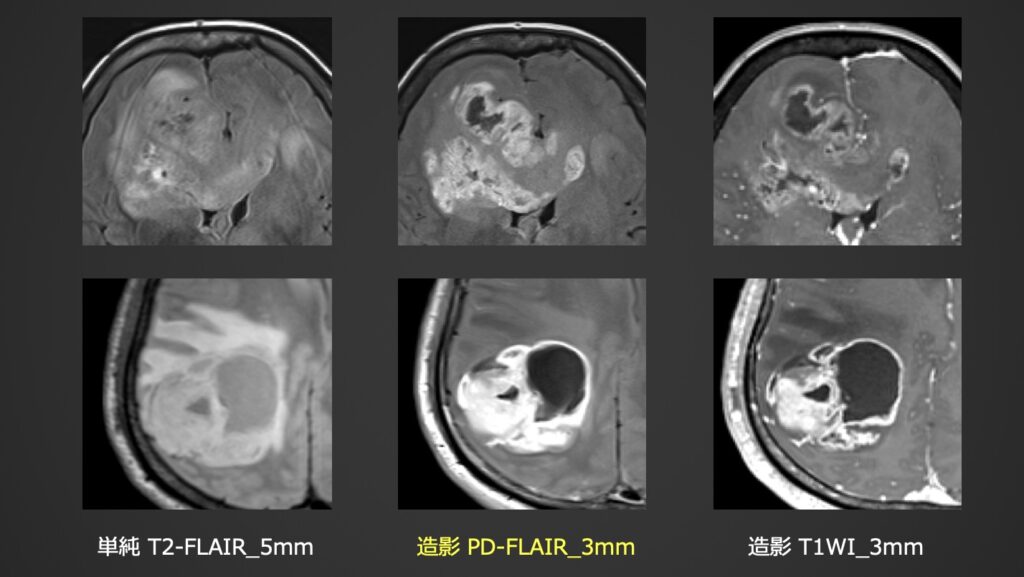

神経膠腫術後精査:長いTI設定による異常硬膜の染め分けと、TE短縮による浮腫コントラストの抑制により浮腫内の造影結節を短時間で同時描出できた症例。